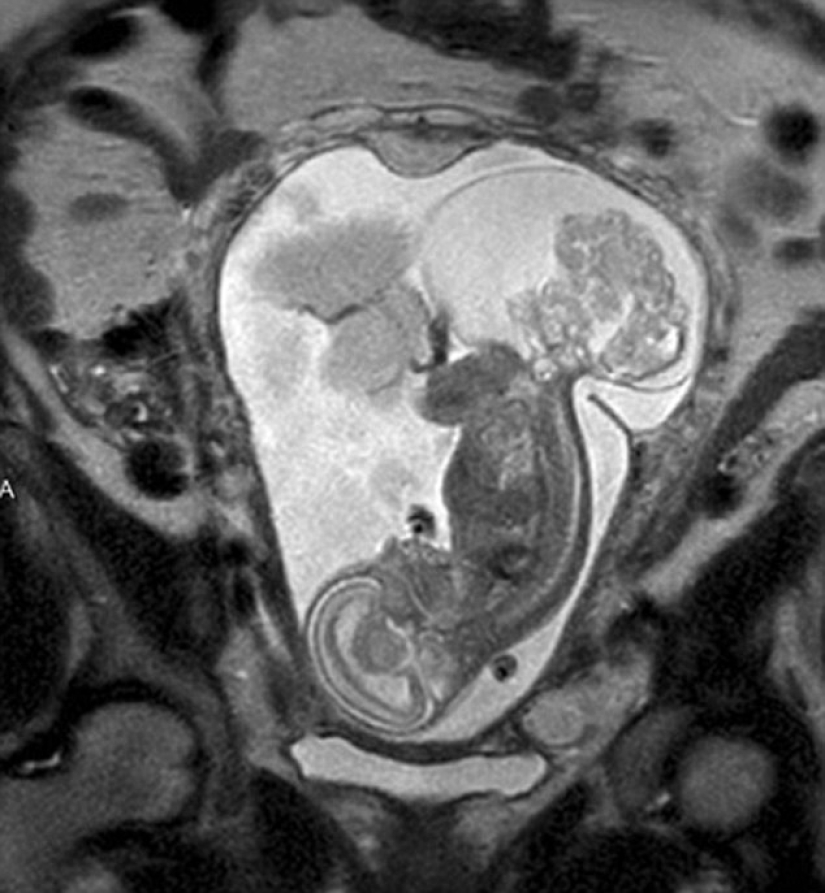

When a resident of Texas, Margaret Bomer, did another ultrasound at the 16th week of pregnancy, doctors told her that the child had a tumor in the coccyx area. The only hope for salvation was an operation during which doctors had to open the womb and take out a fetus weighing 538 g for 20 minutes, and then return it back. The girl's chances were 50/50.

By the time doctors got permission for the operation, Lynley was about 24 weeks old and the tumor was the size of the fetus itself. The operation lasted five hours, but according to Dr. Kass, the part that concerns the child lasts only about 20 minutes. Most of the time it takes to open the uterus. As soon as the surgeons got to the baby, they lifted him up so that he hung in the air. "In fact, the fetus turns out to be outside literally, all the amniotic fluid flows out, and this is a really impressive sight," the doctor says.

During the operation, Lynley's heart slowed down almost to a complete stop, but her life was supported by a separate specialist while surgeons cut out the neoplasm. When they had done all they could, the doctors put Lynley back in the uterus and sewed her up as tightly as possible. "It's like a miracle when you can open the uterus, sew it back up, and everything keeps working," says Dr. Cass.